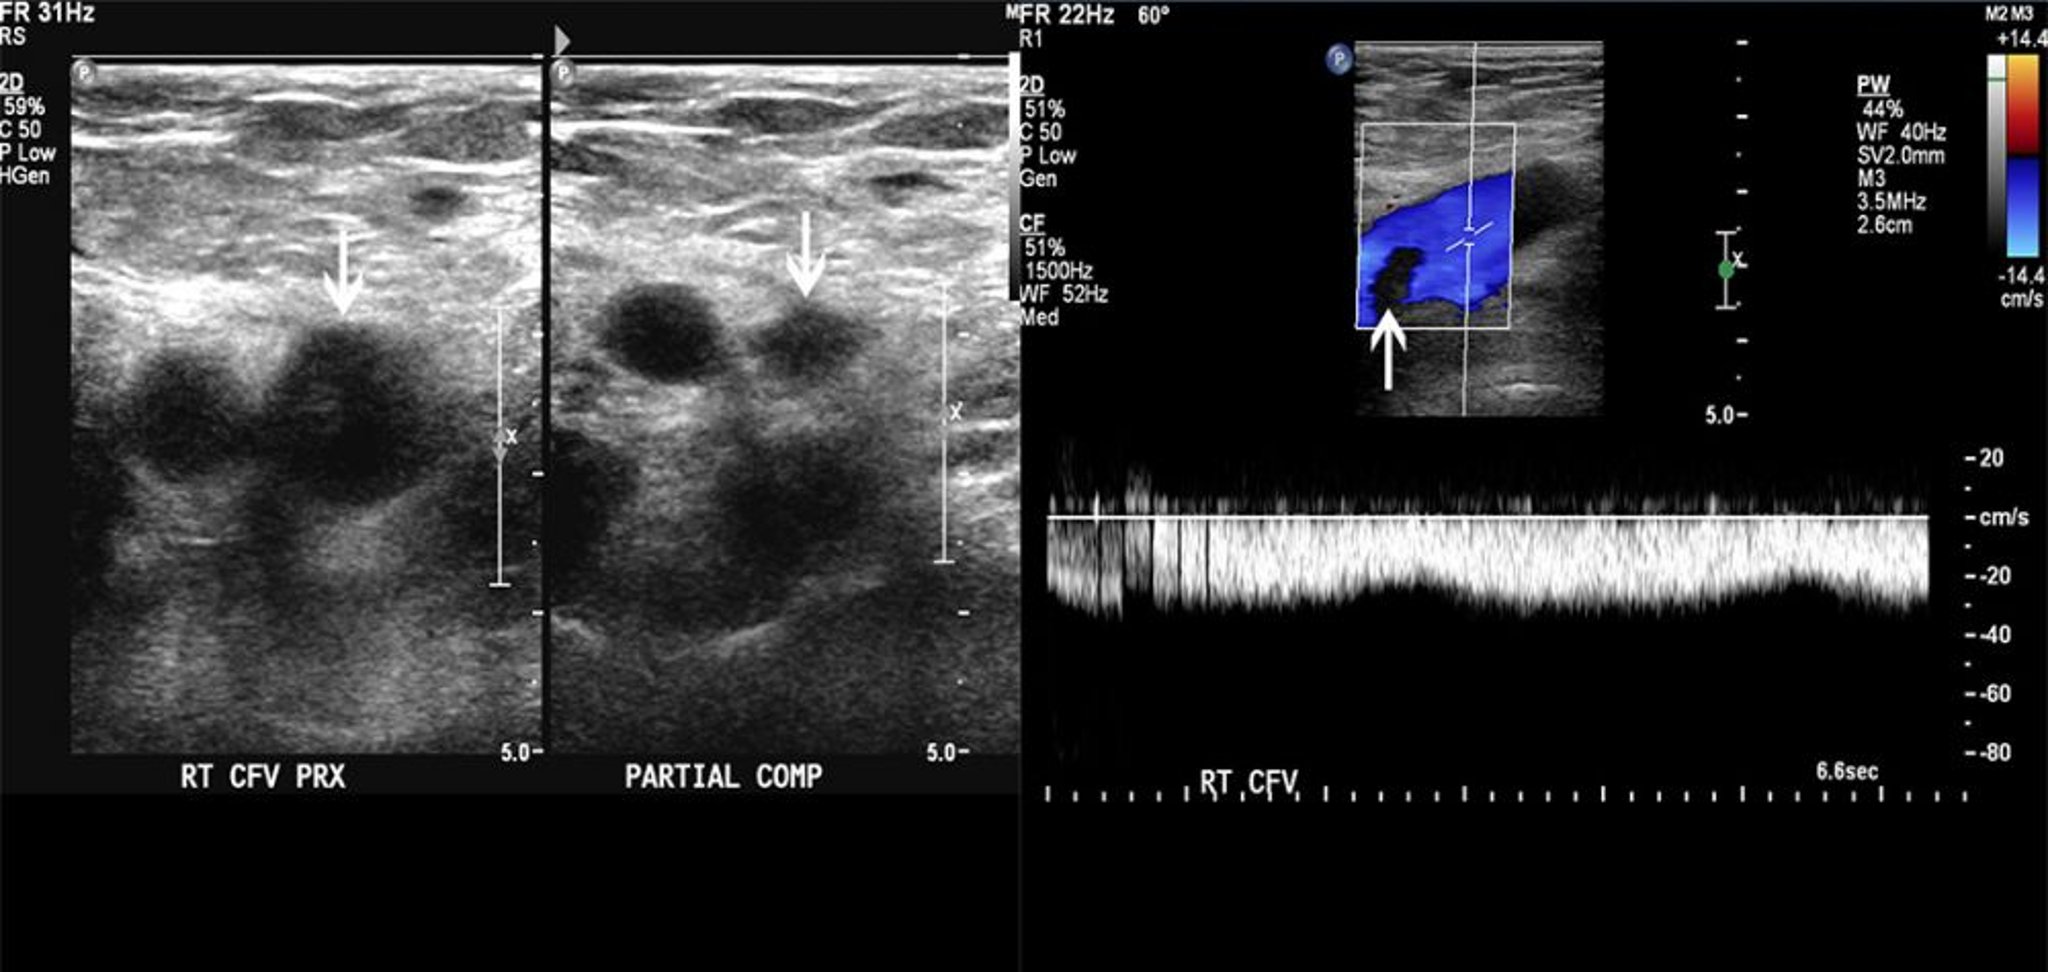

Ecografia

L'ecografia identifica i trombi visualizzando direttamente il rivestimento venoso e dimostrando un'alterata compressibilità venosa o, con studi di flusso Doppler, un flusso venoso compromesso. Il test ha una sensibilità > 90% e una specificità > 95% in caso di trombosi delle vene femorale e poplitea, ma è meno accurato in caso di trombosi delle vene iliache o del polpaccio (1).